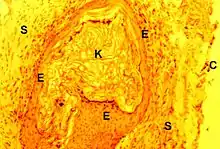

Il est formé par un matériel éosinophile de nature kératinique, squameux et généralement anucléé sauf lorsqu'il existe une parakératose dans l'épithélium pariétal sous-jacent. Des noyaux aplatis et pycnotiques sont alors visibles dans une zone limitée. Il se mêle parfois à la kératine des polynucléaires et des histiocytes plus ou moins fusionnés en cellules géantes (symplasmes). Ces macrophages tendent à englober les lamelles cornées. Ils sont souvent l’indice de discontinuités dans la paroi du « sac » dont ils proviennent et peuvent aussi traduire la présence d’un granulome à kératine sous-jacent.

Lésion prédominante, elle est caractérisée au début par un simple œdème du stroma et une vaso-dilatation de ses capillaires. Un infiltrat inflammatoire non spécifique apparait ensuite dans le même stroma. Cet infiltrat se compose de polynucléaires neutrophiles, lymphocytes B, plasmocytes, mastocytes et histiocytes. Il peut former un ou plusieurs foyers granulomateux avec des capillaires néoformés, des fibroblastes et des hémorragies localisées.Des polynucléaires et cellules de Langherans en émigrent vers l’épithélium malpighien sus-jacent où leurs vimentine et proteine S100 permettent de bien les mettre en évidence. L’afflux de ces cellules inflammatoires peut entrainer des ruptures épithéliales spontanées (ulcérations) et confirme leur agressivité envers le revêtement malpighien[8].

Essentiellement formés par un amas de macrophages se fusionnant en cellules géantes (symplasmes) pourvues de nombreux noyaux, donc multinucléées, ils résultent d’une stimulation locale du stroma. Elle peut être due, soit à des corps étrangers iatrogènes qu’une précédente intervention a introduit dans l’oreille moyenne, soit aux productions pathologiques de cette dernière : kératine du cholestéatome et dépôts de cholestérol. Il s'y associe des infiltrats inflammatoires granulomateux banals à cellules rondes (lymphocytes, plasmocytes) et une vasodilatation des capillaires sanguins plus ou moins marquée.

Les cellules géantes sont du type antixénique. Par leur coloration, leur nombre et la disposition des noyaux, elles se différencient des cellules de Langhans (tuberculose), des ostéoclastes ou myéloplaxes qui sont pourvus d’une « bordure en brosse » (microvilli) et des symplasmes de la maladie de Wegener.

Granulome à cholestérol

Déjà reconnu macroscopiquement par sa couleur dans une douzaine de cas, il montre toujours les constituants habituels de ce type de lésion : fentes aciculaires ou en forme de cigare correspondant à des cristaux cholestéroliques dissous lors de la préparation des coupes (images négatives) ; macrophages et cellules géantes entourant ces cavités. De plus, les capillaires sanguins sont souvent dilatés et à l'origine de foyers hémorragiques. La désintégration de ces derniers est responsable de dépôts d’hémosidérine, granuleux et brun-jaunâtre, se colorant par la technique de Perls au bleu de Prusse. Il peut survenir aussi une hyalinisation homogène et faiblement éosinophile du stroma conjonctif séparant les fentes aciculaires. Le granulome à cholestérol est présent dans 23,5 % des observations.